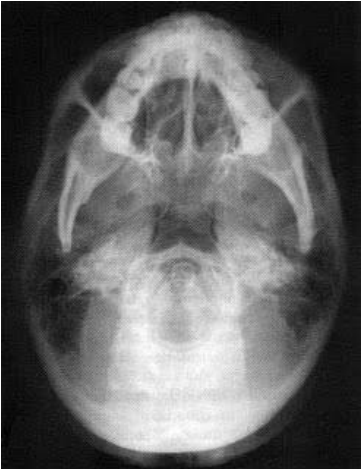

Em relação às incidências para radiografia da face, observa a imagem abaixo.

Trata-se da incidência: